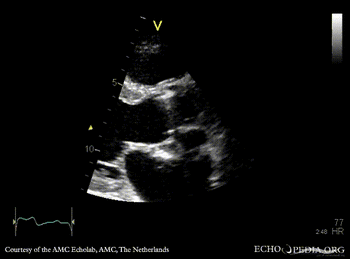

Abscess of aortic valve prosthesis

Courtesy of: AMC Echolab, AMC, The Netherlands

PLAX: abscess of aortic valve prosthesis PLAX with Color Doppler: severe mitral regurgitation